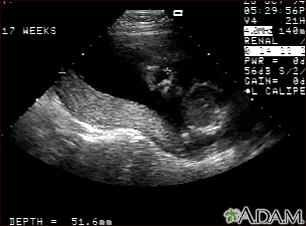

Ultrasound, normal relaxed placentaBackUltrasound, normal relaxed placentaThis is a normal fetal ultrasound performed at 19 weeks gestation. This ultrasound shows two interesting features. In the foreground, to the left and middle of the screen, you can see the placenta, following the curve of the uterus. In the background on the right, where the cross hair is pointing, you can see the face with all the facial features visible. E-mail FormEmail ResultsName:Email address:Recipients Name:Recipients address:Message: